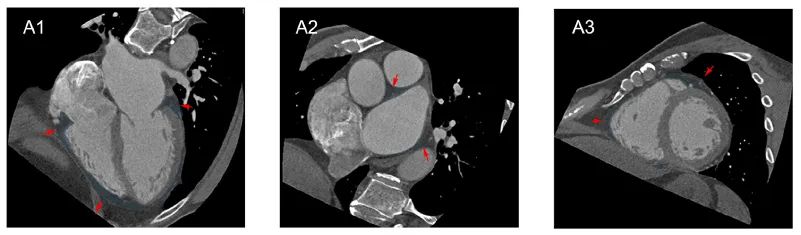

本研究首次揭示了心外膜脂肪组织(EAT)厚度与房颤(AF)之间的正相关性 。 通过对53名患者的详细测量 , 研究者发现房颤患者的EAT平均厚度显著高于对照组 , 其中阵发性房颤和持续性房颤患者的EAT厚度分别为12.9 mm和15.0 mm , 而对照组仅为9.8 mm 。 这一发现为理解EAT在心律失常中的作用提供了新的视角 。

图1:CT测量EAT厚度(A1:右AVG、左AVG和前IVG的水平长轴横截面;A2:食管、主肺动脉和降主动脉处心房周围EAT的短轴横截面;A3:上IVG、下IVG和右心室游离壁的短轴横截面)